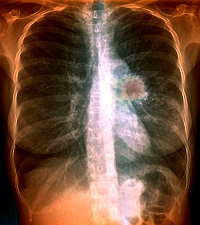

Arra a feltevésre építve, hogy az ösztrogén blokkolása csökkentheti a tüdőrák halálozási kockázatát, svájci és francia kutatók 6655 mellrákos nő esetében vizsgálták a tüdőrák előfordulását és halálozását.

Az 1980 és 2003 között megbetegedett nők mintegy fele, 3066 beteg kapott tamoxifent emlőrákjára, és az adatok szerint a 2007 decemberéig tartó utánkövetési időszakban közülük 87 százalékkal kevesebben haltak meg tüdőrák miatt, mint általában a lakosság körében.